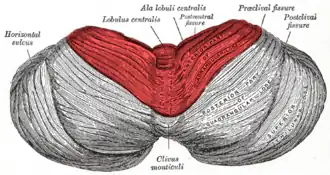

Superior view of an cerebellum. Anterior lobe shown in red. | |

The anterior lobe of cerebellum is one of the lobes of the cerebellum responsible for mediating unconscious proprioception. Inputs into the anterior lobe of the cerebellum are mainly from the spinal cord.[1] It is sometimes equated to the "paleocerebellum".[2]